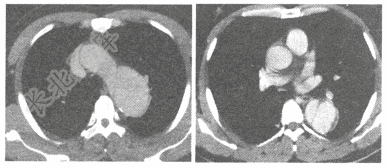

- 单项选择题男,67岁,胸骨后撕裂样疼痛1小时就诊。主动脉CT增强扫描图像如下,应诊断是

D、主动脉夹层动脉瘤